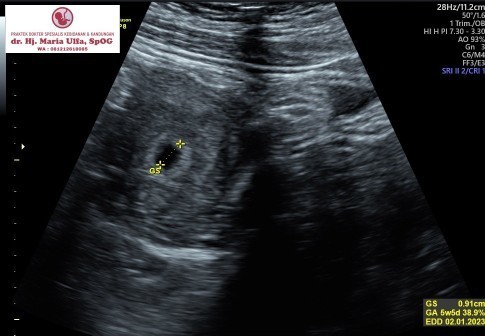

kantung bayi

Bun sy mau tanya, normalkah hamil 6 minggu baru kliatan kantung.a aja atau bagaimana ? Dan ukurannya baru 2cm bun, normalkah ?

Normal bun, sayapun 2 minggu lalu uk 6w5d baru terlihat kantongnya saja ... ☺️☺️

aku td usg kliatan kantong janinnya aja masih imut usia kandungan 5minggu 5 hari